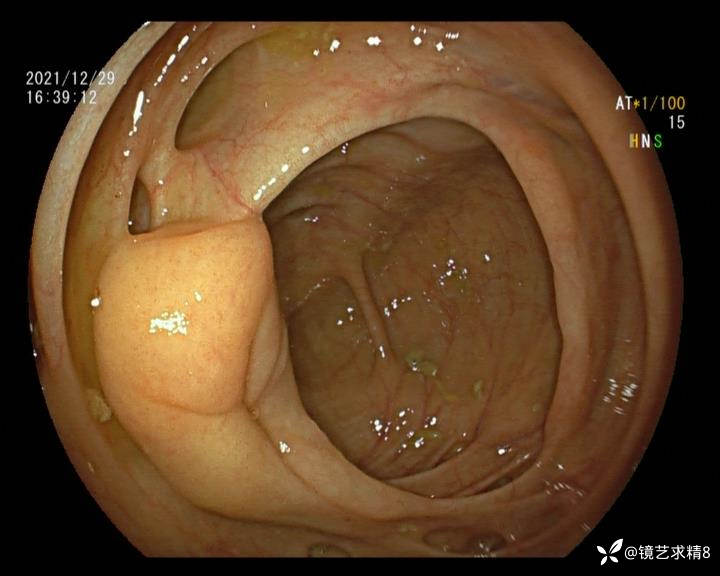

结肠内违建⥤结肠多发憩室☞续

小壮兵爱学习等 2人推荐看到手机存有2年前一个病例仅有的3张图片,因为没有更多的图片就只描述了多发憩室这个内容,没想到浏览量很快上万,很多都和我一样第一次见这么多憩室的结肠,就不得不想要把2年前所有的片子拷贝出来分享。该病例憩室合并外源性因素成为憩室出血的原因。后面附有代表性的全结肠图片。

患者以消化道出血入院,胃镜未见异常,肠镜进入乙状结肠就看到很多憩室,同时还看到肠腔用清肠药后移动下来1枚尖锐的枣核,这么多憩室,这个枣核扎入憩室的机会非常大,推测应该是掉入一坑🕳就算出来还会有很多坑🕳🕳🕳等着,掉入憩室内很容易刺破血管,这可能就是消化道出血的原因,继续前进可以看到有一些憩室内翻,还有一些息肉,问题来了,那么多憩室,犯罪分子是抓住了,它在那些憩室内作过案?到达回盲部后挨个冲洗,但憩室大小又不足以把镜头进入憩室内观察,针对有血块的憩室冲洗后可疑出血的以夹子闭合或套扎,取出枣核,如果有锥形透明帽可能钻入憩室精准电凝效果更好,若内镜下操作失败介入治疗成功率更高,经内镜下治疗后观察未再出血出院。